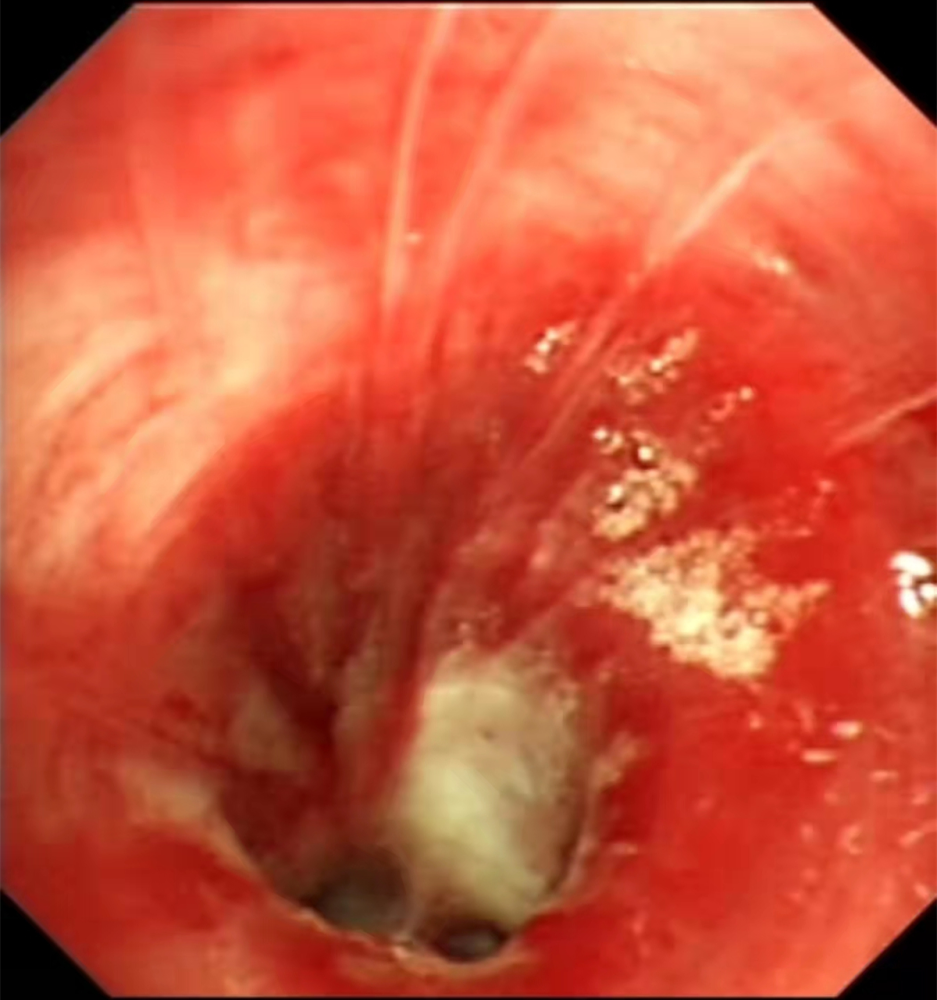

吸入性肺炎 (co中毒后误吸致右侧肺炎)